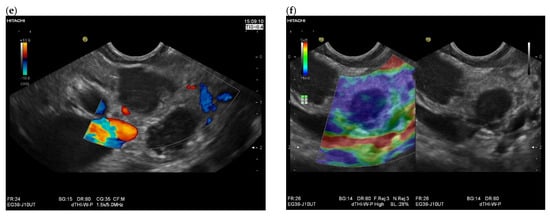

| Colour Doppler Imaging | RCC metastases are hypervascularized Most other pancreatic metastases are hypovascularized | No hypervascularization | Hypervascularized |

| RCC metastases [83] (n = 4) | Hyperenhancement, Early | Hyperenhancement | ||

| RCC metastases [61] (n = 3) | Hyperenhancement, homogeneous pattern | Slow washout | ||

| RCC metastasis [86] (n = 1) | Hyperenhancement, Inhomogeneous pattern | No washout | ||